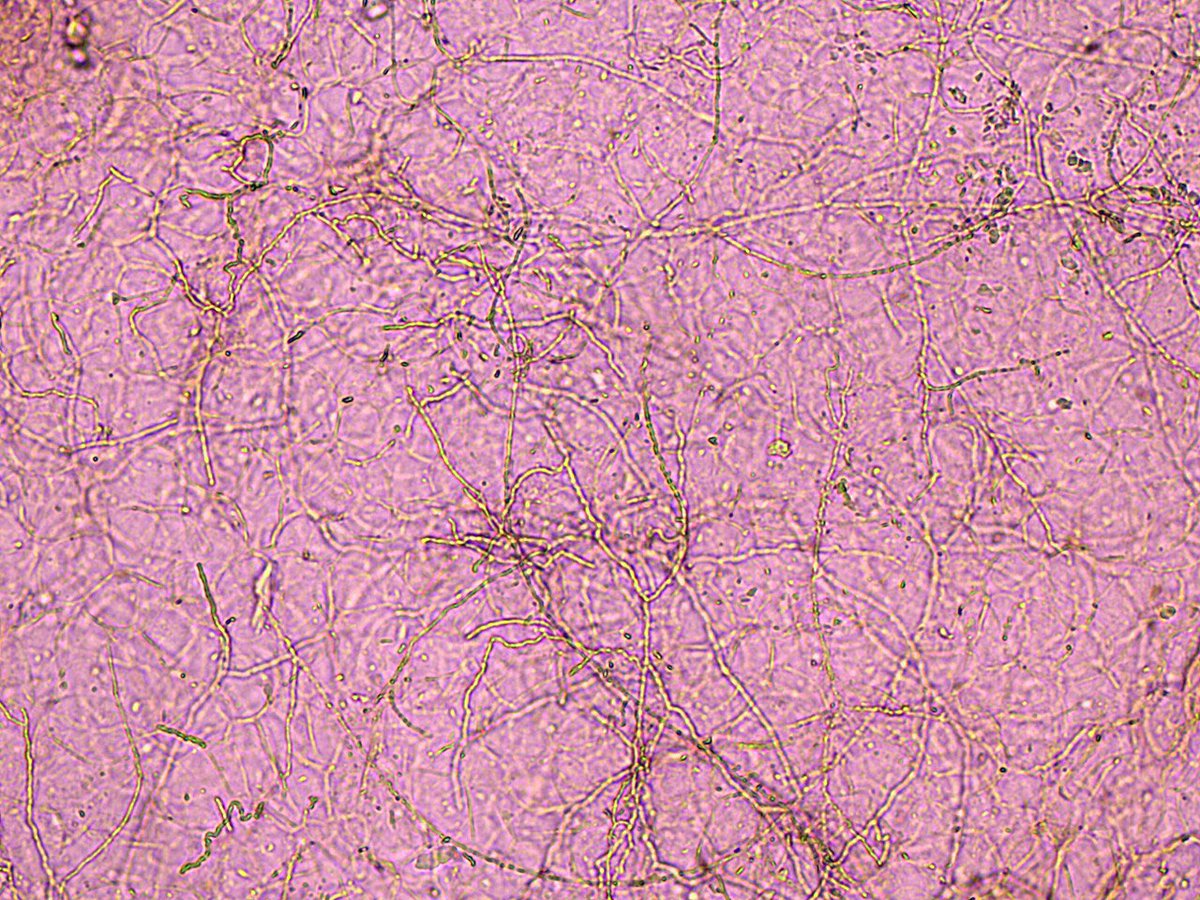

Onicomicosis . Detalle : micelio desarticulado en artrosporas

2

8

51